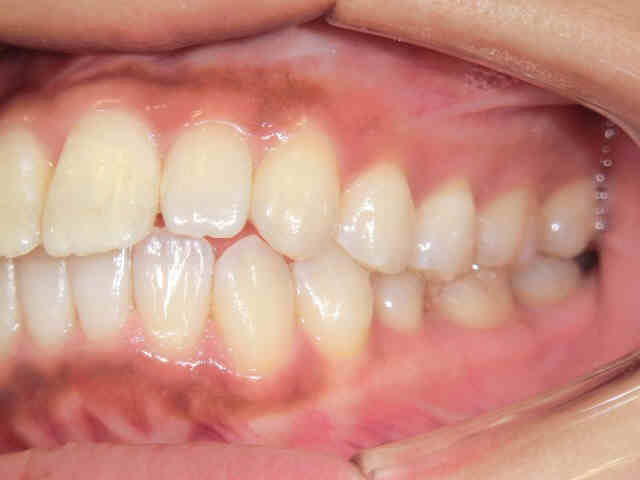

左右から見た噛み合わせの状態では、緊密な咬合が観察されます。